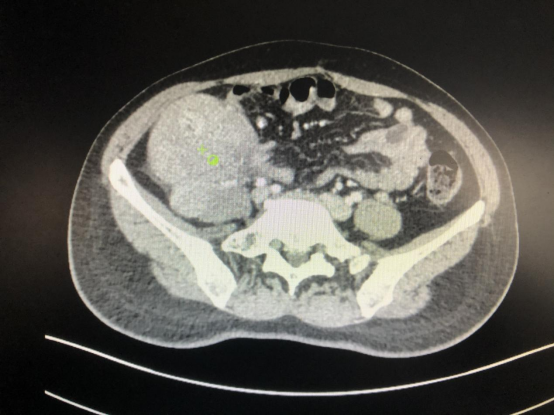

近日,我院普外科一病区成功为一名38岁女性患者郑某某(化名)实施了腹膜后肿瘤切除手术。患者因右下腹包块伴反复发热2月来院就诊。入院CT检查提示右下腹有直径达13cm的占位性病变;左侧附件区也存在囊性灶。